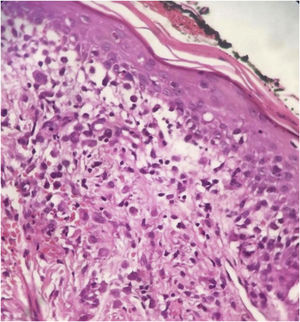

Histopathology revealed chronic dermatitis associated with the presence of cells suggestive of Langerhans cells (Fig. 2). Immunohistochemistry showed positivity for CD1a, CD68, S100 protein; Ki67 was positive in 70% of the cells (Fig. 3). Once the diagnosis of LCH was confirmed, the investigation of other organs through a myelogram and computed tomography of the chest, abdomen, and pelvis led to the classification of the case as multisystemic LCH due to pulmonary and hepatic involvement. Treatment was started with weekly vinblastine 3 mg/m2 + prednisone 20 mg/m2, according to the Brazilian Society of Histiocytosis guideline. The condition improved significantly, but after about two months the skin lesions returned, and the pulmonary condition worsened, requiring oxygen therapy. A new chemotherapy regimen with Cladribine (2-CdA) was introduced, according to the Japanese protocol. The patient remains stable and is being followed by the oncology team.

The diagnosis depends on the clinical, anatomopathological and immunohistochemical correlation. Histopathologically, varying amounts of Langerhans cells with a “coffee bean” appearance are observed. Positive immunohistochemistry for CD1a and CD207 (langerin) establishes the diagnosis.5